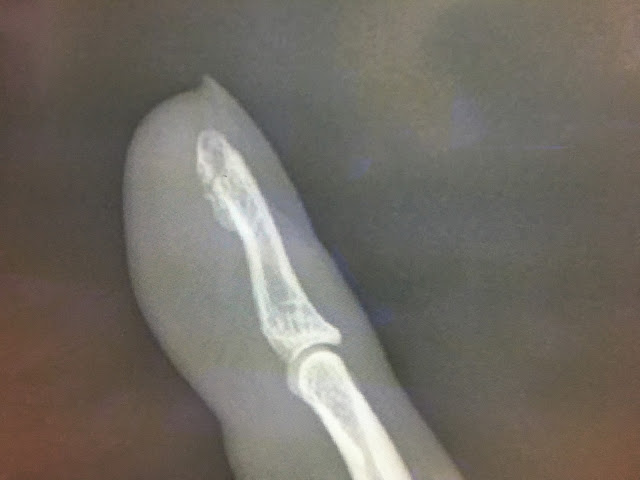

骨折

薬指骨折。

触ると飛び上がるぐらい痛いw